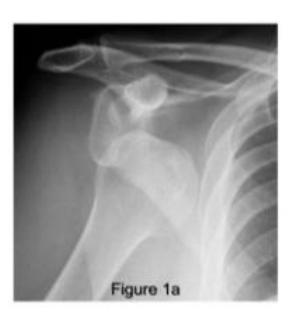

18-year-old male presented after sport injury and unable to do internal rotation of right shoulder. What is the name of the injury seen in the figure?

- Hill-Sachโs defect

18-year-old male presented after sport injury and unable to internally rotate his left shoulder. What is the diagnosis?

- Hill-Sachs lesion

A case scenario about a male with anterior shoulder dislocation. What does the figure 1b show?

reverse - Hill sachs lesion

What do you see in this image?

- Hill sachs lesion